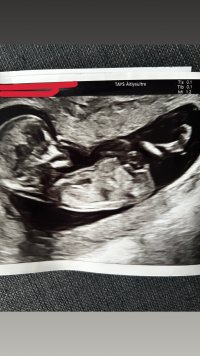

NT-ultra käyty. Kaikki näytti olevan kunnossa ja terve tyyppi tulossa näiden tietojen mukaan. LA olisi ultran mukaan 12.1 mutta ei vaihdeta vaan pidetään 16.1. Istukka etuseinässä ja alhaalla mutta ei kuulemma tarvitse huolehtia.

Sydän pompotti nätisti ja pikku veikka oli rauhallista sorttia, unten mailla.

Sai hyvin ultrattua kaikki elimet ja raajat. Nyt odotellaan seulonnan tarkempia tuloksia ja jännitetään onko poika vai tyttö. Päätettiin ottaa selvää kumpi on tulossa. 8 pitkää ja lyhyttä päivää odotusta. Seuraava rakenneultra viikolla 21.

Okei joo mä jotain yritinki tosta nub-teoriasta lukea, mutta en mä tajunnut mitä siitä kuvasta pitäisi nähdä. Ultraaja sano kyllä silloin, että erinomainen näkyvyys ja viikkoja oli 13+1. Ehkä voisin kuvan tänne pudottaa, jos joku haluisi arvailla😅 Mulla vaan neuvolla rv 18 ja sit sen jälkeen rakenneultra eli mahollisesti vasta sillon tarkan tiedon saa, mutta tokihan sekin voi erehtyä. Minusta aikoinaan luultiin syntymään asti, että poika tulossa, mutta sitten tyttö olinkin😄